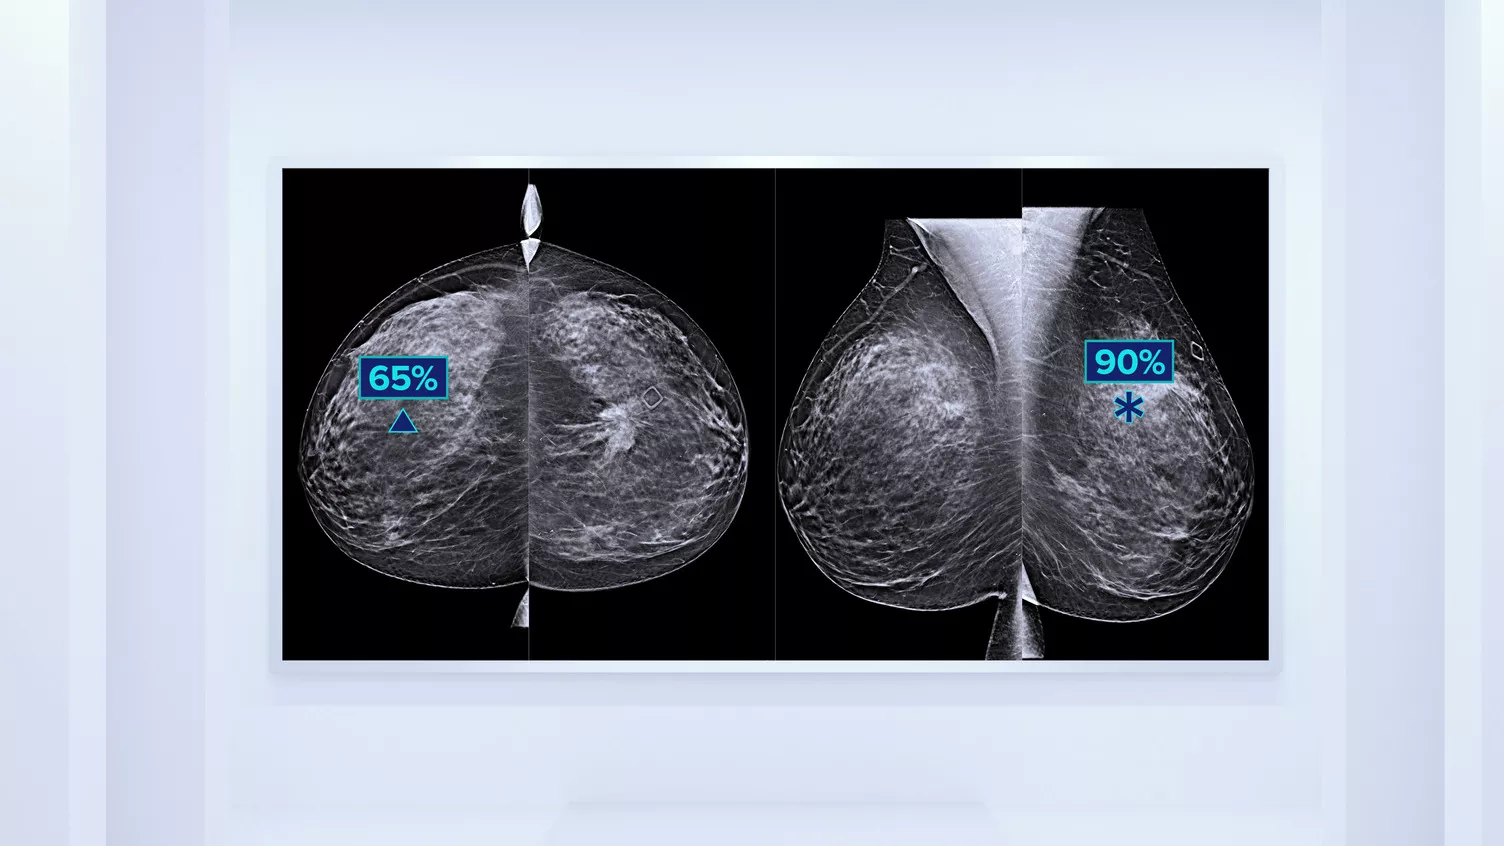

In addition to volume, pattern and texture of fibroglandular tissue may play just as an important role in mammographic cancer risk prediction.3-5 By analysing and categorising breast texture and pattern, our technology can deliver the accurate information you need to achieve more consistent and reliable scoring and confidently design patient-specific screening.

Objective machine learning algorithm that assigns breast density category based on analysis of breast tissue texture and patterns.

• Overcoming subjectivity in visual assessment, providing more consistent, and more reliable scoring.*